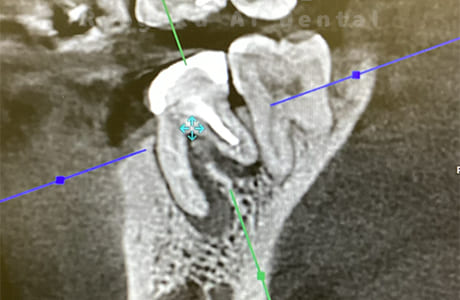

CTスキャンによる診断

すべての歯科治療において診査診断は非常に重要です。

CTスキャンによる検査をすることで歯根の状態をしっかり把握し治療計画を立てることができます。

診査診断をしっかりすることで治療の質の向上につながります。